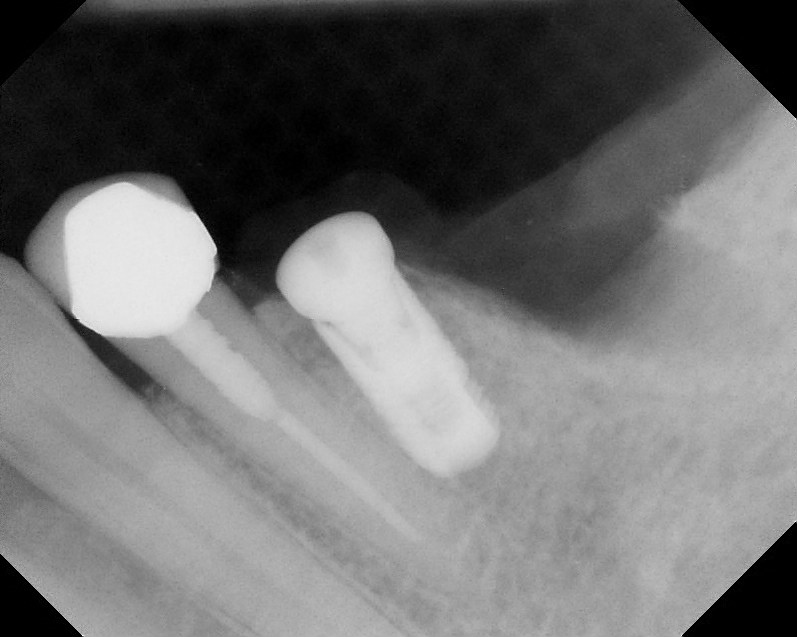

Implants

This treatment involves implanting artificial dental roots, and restoring dental crown without damaging the adjacent teeth.